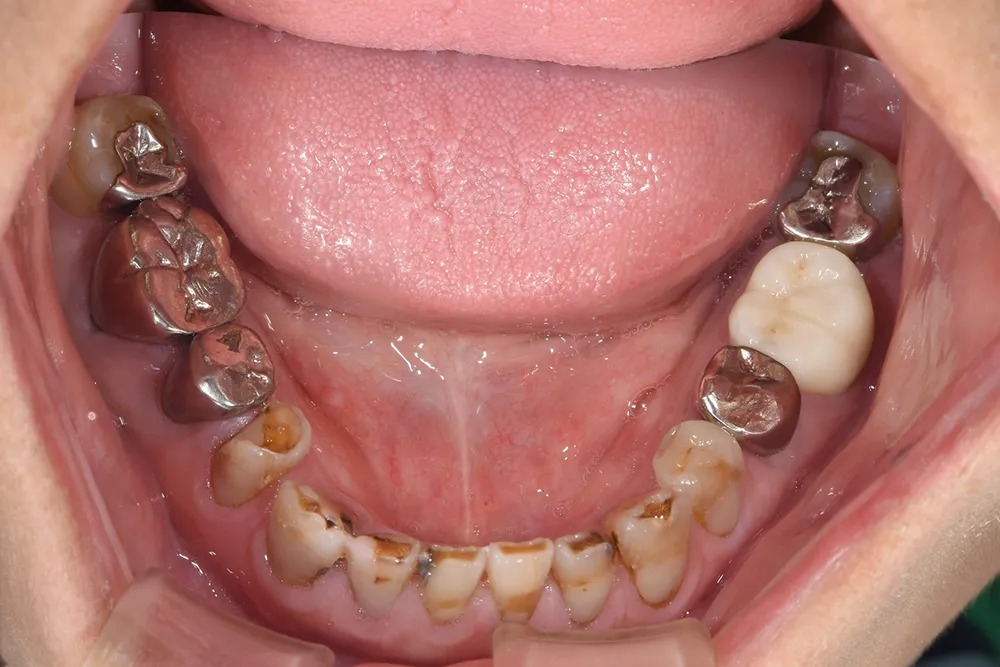

審美歯科治療例8

金属でつめてあったものを、オールセラミックにやりかえたケースです。

従来は金属の詰め物ですが、点線で囲んだ部分はオールセラミックです。

主訴 金属の詰め物を白くしたい

治療方法 金属の詰め物を除去し、セラミックで治療を行った

治療期間 約1ヶ月

通院回数等 4回

費用 66,000円(税込)

リスク・副作用 色調を合わせるのが難しい